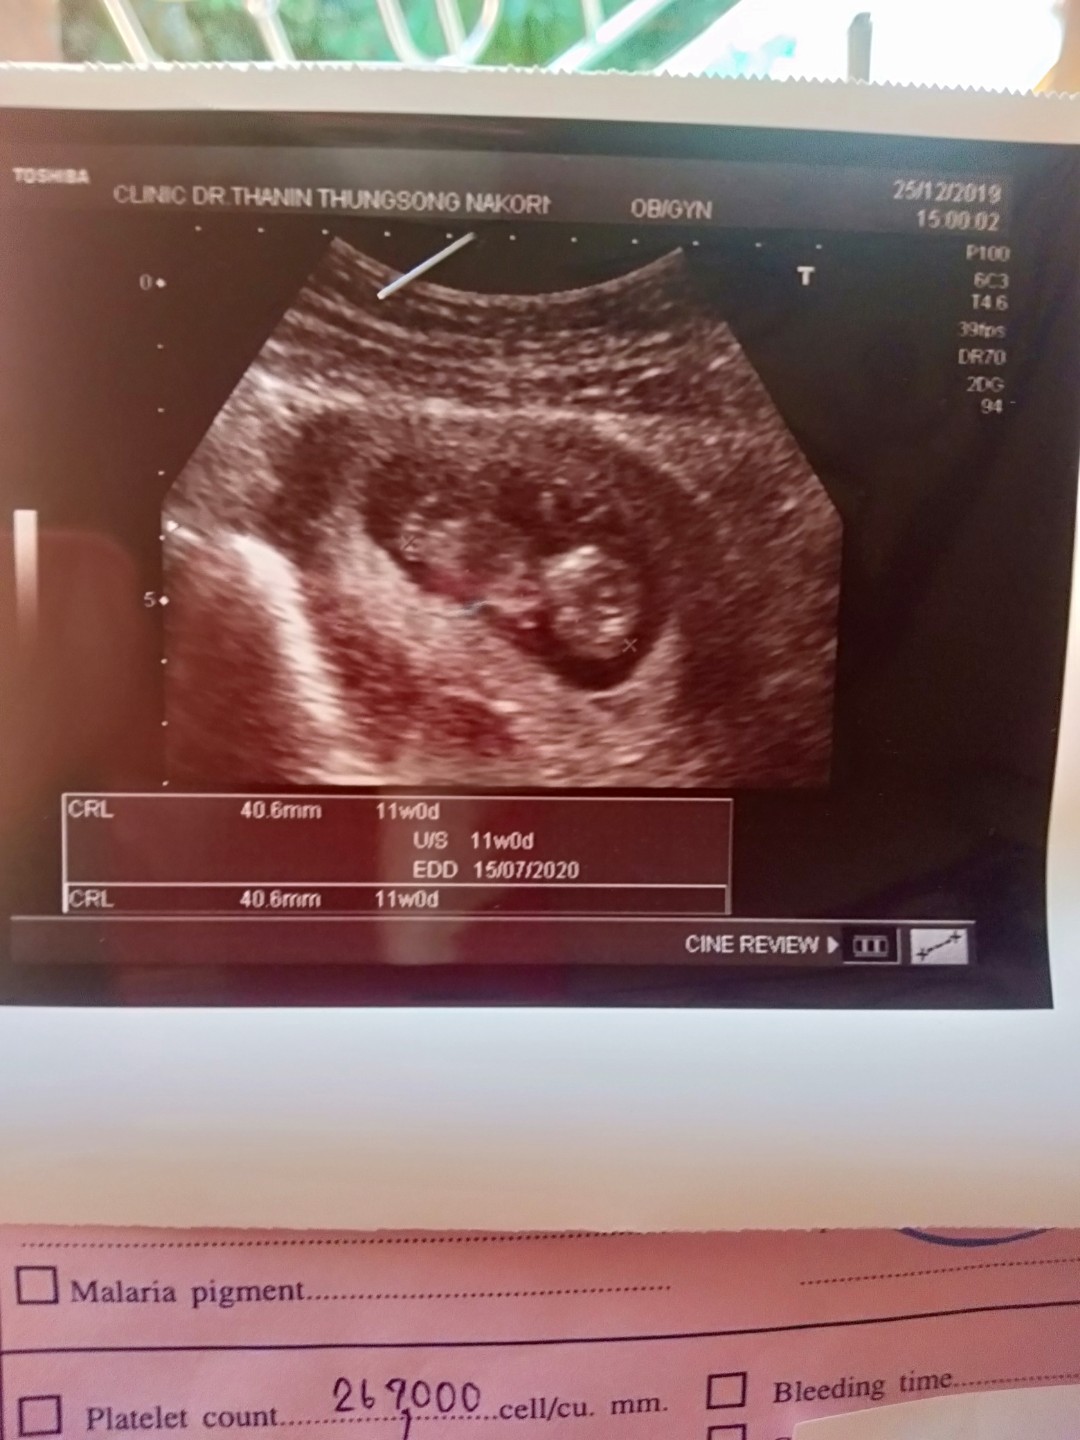

ตอน11wค่ะ